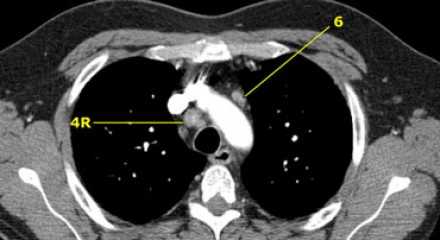

На изображении слева мы видим 4R паратрахеальные узлы. Кроме того здесь представлен узел кнаружи от дуги аорты, то есть 6 группы.

Узлы 5 группы (аортопульмонального окна) расположены кнаружи от артериальной связки.